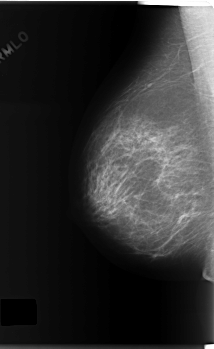

C_0165_1.RIGHT_CC

RIGHT_CC LINES 5896 PIXELS_PER_LINE 3424 BITS_PER_PIXEL 12 RESOLUTION 50 NON_OVERLAY